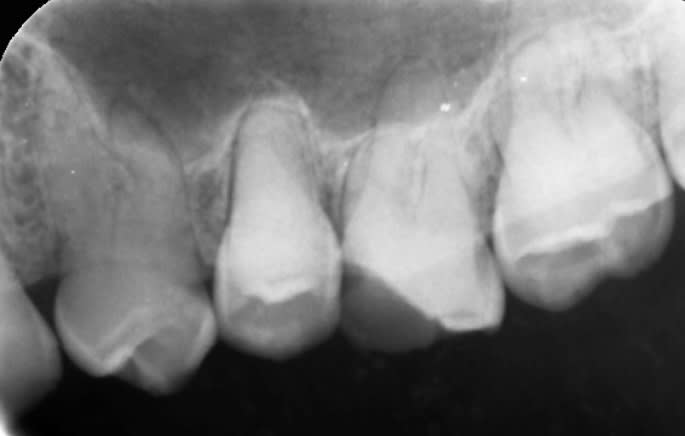

Radio 11

8af24b3d fd05 4021 a759 7a5e9e05a6a7 h5jlk1 - Eugenol